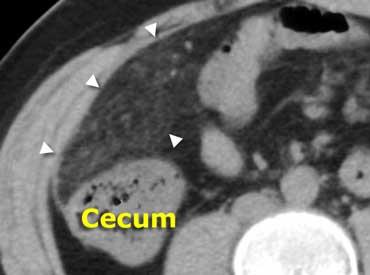

Siêu âm điển hình cho thấy dày thành dưới niêm mạc (đầu mũi tên) của hồi tràng đoạn cuối và manh tràng mà không có viêm mỡ xung quanh.

Viêm hồi manh tràng do vi khuẩn

Viêm ruột nhiễm khuẩn có thể gây ra các triệu chứng nhẹ giống viêm dạ dày ruột do virus thông thường, nhưng cũng có thể biểu hiện lâm sàng với các đặc điểm không thể phân biệt được với viêm ruột thừa, đặc biệt trong viêm hồi manh tràng do vi khuẩn, gây ra bởi Yersinia, Campylobacter hoặc Salmonella.

Dấu hiệu chính: Dày thành hồi manh tràng không kèm viêm mỡ, hạch to, ruột thừa bình thường